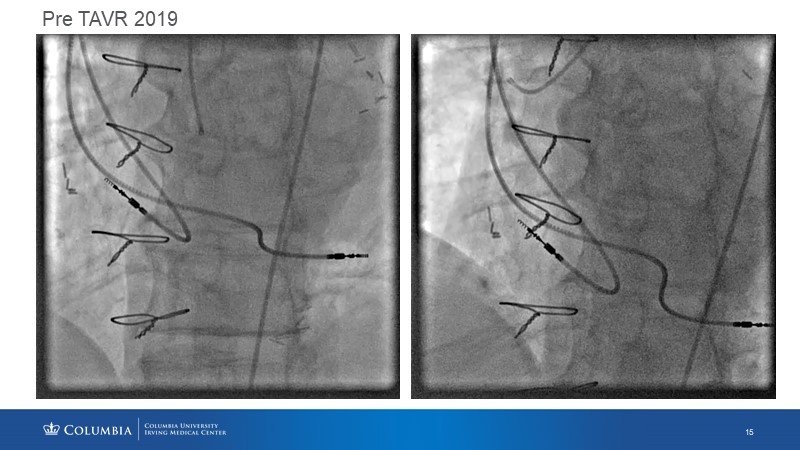

Through the presentation of real-life clinical cases, this session will allow you to discover the use of ALLEGRA for valve-in-valve TAVI, understand the management of coronary artery disease in TAVI patients, better detect when and how to protect coronary arteries during TAVI, or even learn how to perform commissural alignment with ALLEGRA.